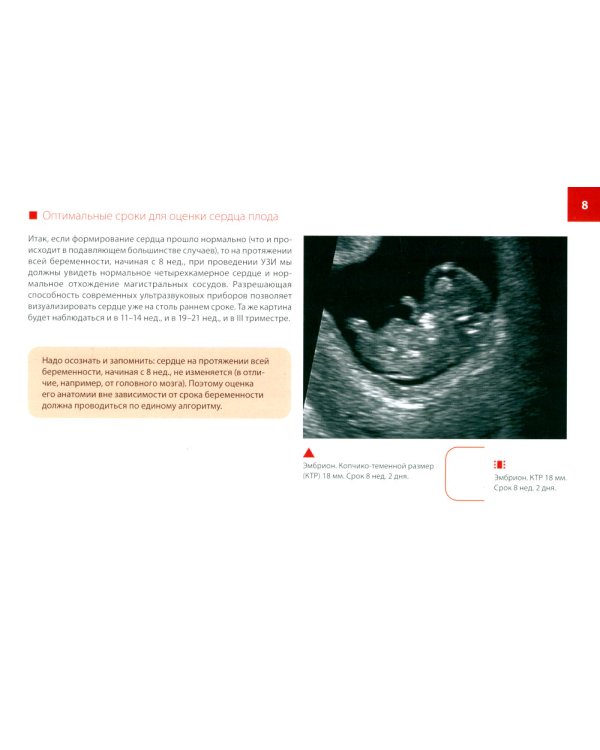

В книге представлены основные анатомические структуры сердца, доступные для оценки с помощью ультразвука во время беременности. Определены оптимальные сроки проведения исследования. Пошагово разобран алгоритм оценки ультразвуковой топографической анатомии в I, II и III триместрах беременности. Пособие предназначено для врачей ультразвуковой диагностики, специалистов пренатальной диагностики, акушеров-гинекологов, перинатологов, а также студентов и ординаторов медицинских вузов.| Издательство | МЕДпресс-информ |